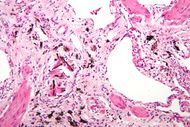

| Micrograph of asbestosis (with ferruginous bodies), a type of pneumoconiosis. H&E stain. | |

2ـ السحار بالأسبست (الأميانت) asbestosis: وهو تغبر الرئتين بغبار الأميانت وهي سيليكات معدنية ليفية تدخل في الصناعات العديدة، والتي تقدر بأكثر من ثلاثة آلاف مهنة في أوربا تستخدم ألياف الأسبست التي منها أنواع عديدة:

تحدث الأذية الرئوية نتيجة الاستنشاق المديد لغبار الأسبست (10 إلى 20سنة) وترتبط بشدة التعرض ولا تظهر الأعراض عادة إلا بعد التعرض المديد وخلال فترة طويلة من ترك العمل تتجاوز العشرين سنة أحياناً. ويشكو المصابون زلة تنفسية ويلاحظ تبقرط الأصابع clubbing (أي زيادة عرض السلامة الأخيرة وتحدب الأظافر نحو راحة اليد مما يعطي الأصابع شكل مضرب الطبل) وقد لوحظ أن الإصابة لا تقتصر على الأشخاص الذين هم باحتكاك مباشر مع غبار الأسبست فقد سجلت حالات عديدة لدى تعرضهم تعرضاً معتدلاً كعمال الدهان والكهرباء الذين يعملون جنباً إلى جنب مع عمال العزل في أحواض بناء السفن وحتى لدى زوجات العاملين في تحضير وتصنيع ألياف الاسبست واللواتي يغسلن ثياب أزواجهن، كما شوهدت حالات من الميزوتليوما الجنبية (أورام الوريقة المتوسطة) لدى القاطنين إلى جوار مصنع الأسبست في لندن والقاطنين بجوار مصنع تعدين الأسبست في جنوب أفريقيا.

إن الإصابة الرئوية التالية لاستنشاق الأسبست تشمل مايلي: حدوث التليف الرئوي الكتلي المترقي progressive massive fibrosis، وسرطان الرئة lung cancer، وورم المتوسطة الجنبية mesothelioma، وانصبابات الجنب pleural effusion، ولويحات الجنب الحميدة أو تليف الجنب pleural fibrosis.

أ ـ التليف الرئوي الكتلي المترقي P.M.F ويتظاهر بالبدء التدريجي مع ترقي زلة جهديه ونقص في تحمل الجهد إضافة لبعض الأعراض كالسعال والقشع عند غير المدخنين. ويعتمد التشخيص على وجود المظاهر الشعاعية من كثافات عقيدية وارتشاحات خطية غير منتظمة تظهر في الأقسام السفلية من الرئتين في البدء ثم تمتد للساحات الوسطى والعلوية مع تقدم الإصابة. ويتطور التليف الرئوي لدى 12 إلى 15% من الأشخاص المعرضين إذ يشاهد منظر الزجاج المغشى، ومع ترقي الإصابة يلاحظ منظر عش النحل بشكل ارتشاحات عقيدية مع ظلال فراغية هوائية، كما يكشف وجود تبقرط الأصابع في40% من الحالات. ويتطور القلب الرئوي في المراحل المتقدمة من التليف الرئوي كما تلاحظ الزرقة الشديدة.